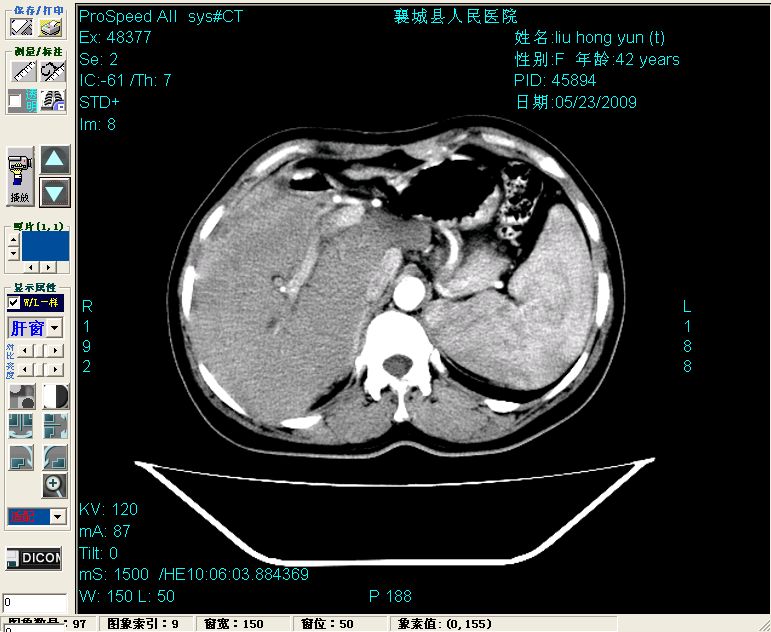

平扫:

平扫左肝外叶体积显著减小,左肝外叶见多房囊性低密度区,左肝实质及右肝前叶浅表实质呈低密度改变,左肝及右肝前叶胆管扩张,脾大

增强动脉期前述低密度区轻度早其强化,门脉期强化程度显著增高,延期扫描强化程度下降,但仍为相对高密度影

胰头部见结节状高密度影,其前方略可分辨扩强胆部管,平扫到增强始终有,但现在尚难与胃肠造影剂鉴别.

结合病史考虑,1现在引起黄疸体征的原因应该是胆总管胰段结石阻塞,建议局部胃肠造影剂排空后复查.

2左肝及右肝前叶表现考虑胆囊摘除术后所致的肝动门脉瘘形成,慢性纤维组织炎性增生.不完全除外左肝胆管细胞癌

3脾大,可能与动门脉瘘所致门脉高压有关